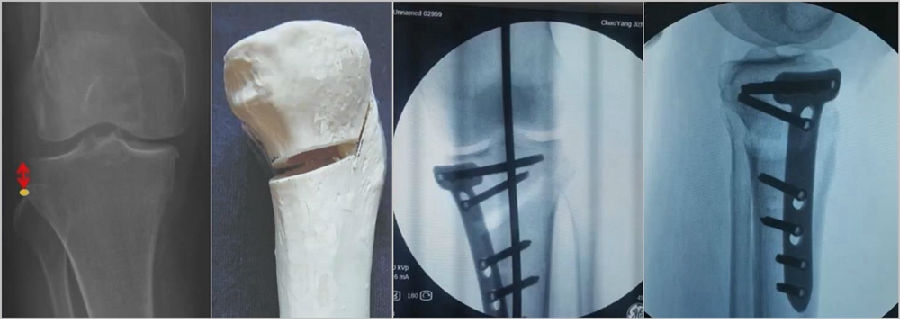

(3)Ⅲ型骨折

首先要把截骨撑开钳拿下来,此时骨折端会自动复位,然后再由外向内侧打入一颗拉力螺钉,将胫骨平台做临时固定,然后再进一步的用摆锯锯或是用骨刀打,保留1cm的合页,最后再进行撑开,做内固定。同样要求患者做结构植骨加延迟负重。

截骨偏前,截骨线过短;Ⅲ型骨折;保留1cm合页

结构植骨,外侧拉力钉固定